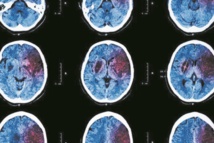

Et si derrière un AVC ou une crise cardiaque se cachaient les prémisces d'un cancer ? C'est ce que semble mettre en évidence une étude publiée dans le journal Blood. D'après les observations de chercheurs de New York, les personnes atteintes d'un cancer sont davantage susceptibles d'avoir eu une crise cardiaque ou un AVC durant les mois précédant leur diagnostic de cancer. Les cancers du poumon et du côlon, ainsi que les cancers à un stade avancé, semblent être les plus fortement associés à ce risque cardiovasculaire.

"Nos données montrent qu'il existe un risque associé d'accident vasculaire cérébral ischémique et d'attaque cardiaque qui commence à augmenter au cours des 5 mois précédant le diagnostic officiel du cancer et atteint un sommet le mois précédent" a déclaré l'auteur principal de l'étude, Babak Navi, professeur agrégé de neurologie. Le cancer aurait ainsi un effet sur le système de coagulation et pourrait bien être le principal facteur de risque associé aux crises cardiaques et aux accidents vasculaires cérébraux.

Pour parvenir à ces conclusions, les scientifiques ont examiné le risque de crise cardiaque et d'AVC chez les personnes âgées de 67 ans et plus chez lesquelles un diagnostic récent de cancer du sein, du poumon, colorectal, de la prostate, de la vessie, de lymphomes non hodgkiniens, de cancers de l'utérus, du pancréas et de l'estomac, avait été établi entre le 1er janvier 2005 et le 31 décembre 2013. Ces cancers représentent les deux tiers de tous les cancers diagnostiqués aux Etats-Unis. L'étude totalisait 748.662 personnes. Ils ont alors pu observer que le risque d'avoir une crise cardiaque et un accident vasculaire cérébral augmentait de 70% au cours de l'année précédant le diagnostic de cancer. Pour le Dr Navi "si une personne a une crise cardiaque ou un accident vasculaire cérébral et qu'il y a des signes inquiétants d'une tumeur maligne non diagnostiquée, telle qu'une perte de poids ou une anémie inexpliquée, peut-être qu'un dépistage du cancer devrait être envisagé".